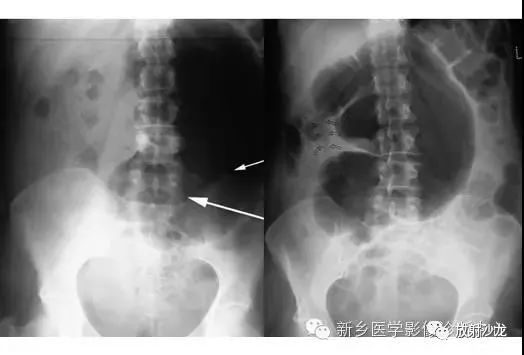

上图腹部平片检查是一6岁男孩,出现呕吐和急性右髂窝疼痛进行的。两个关键的发现在哪里?(提示:通过放射科医生所提供的箭头可以缩小关注点。)

右髂窝多个扩张的小肠襻出现小的钙化结节。小肠袢可与大肠区分开来,因为小肠的环状襞延伸至整个肠壁,而结肠袋只是部分延伸存在。在右下腹(箭头)的钙化结节高度提示阑尾粘连。这个病人开腹手术发现阑尾粘连致小肠梗阻。